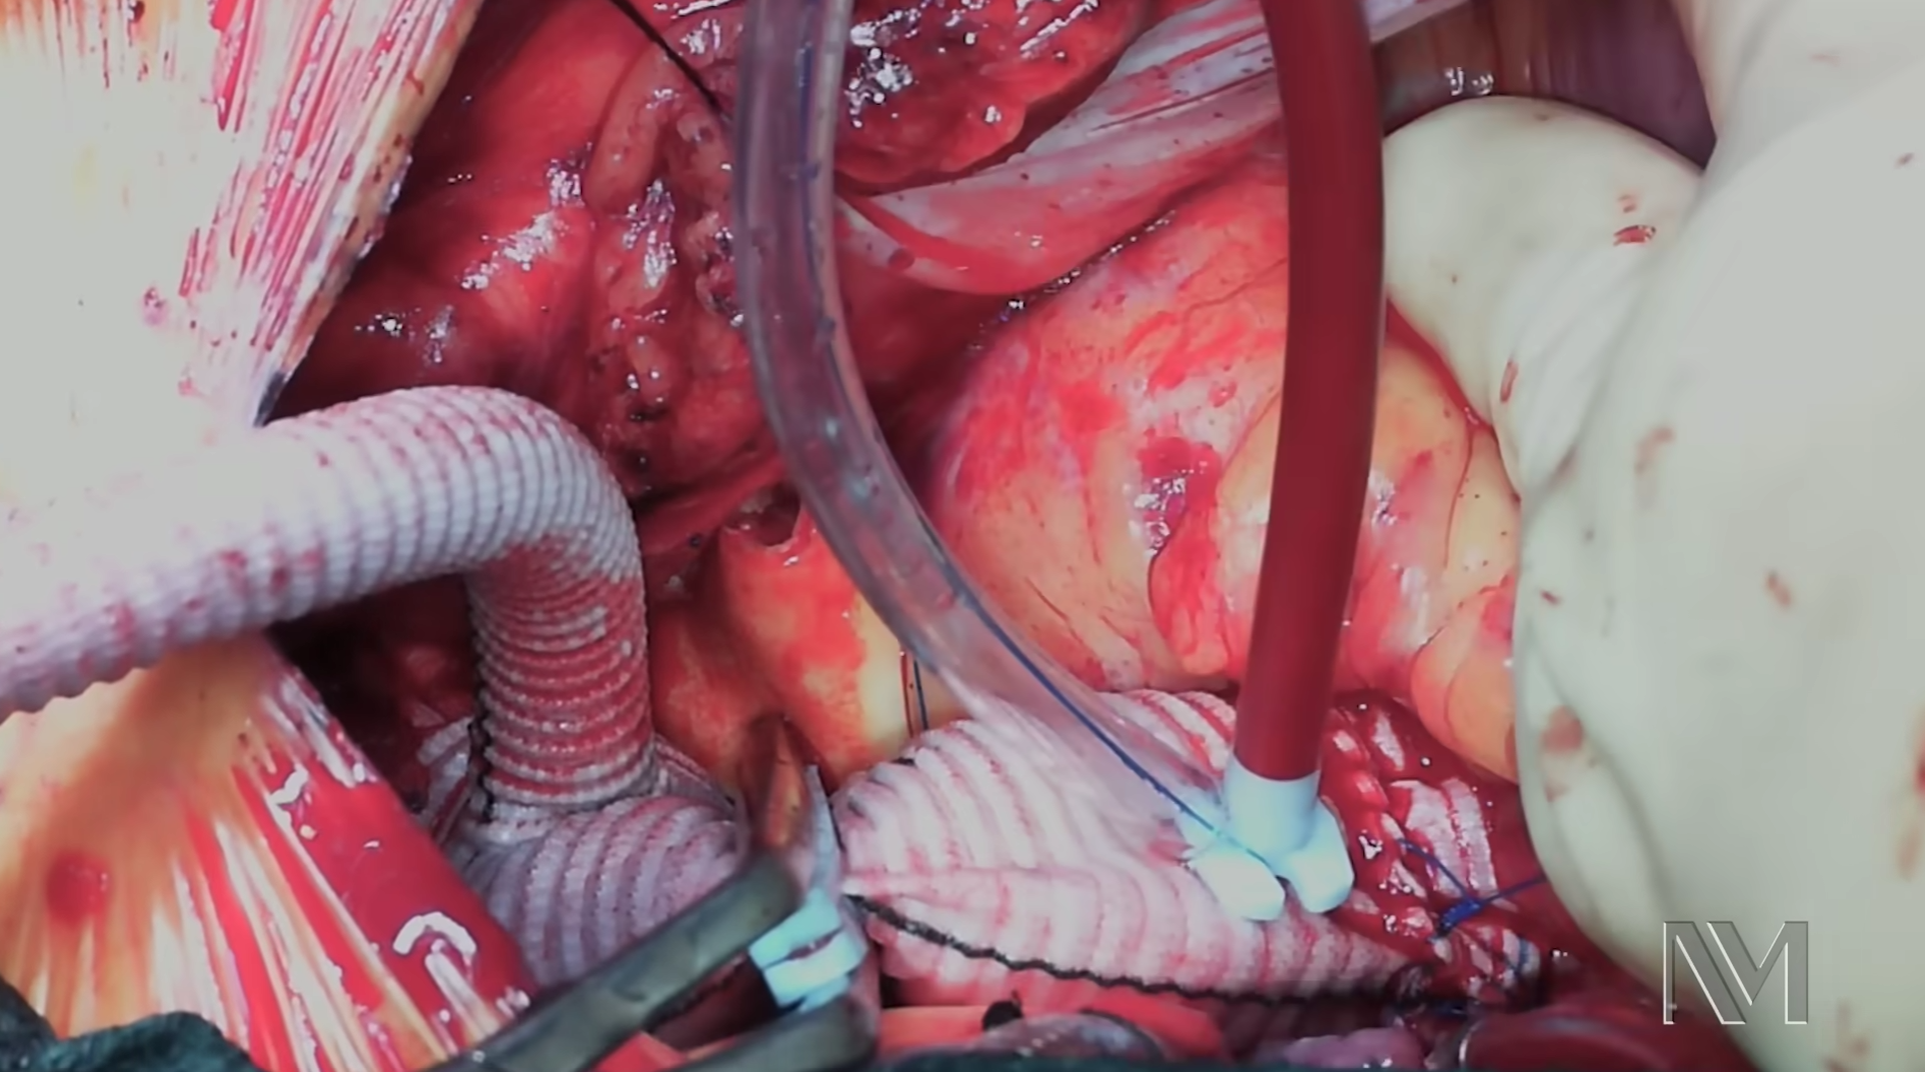

Cilt Grefti Uygulaması

Plastik Ve Rekonstrüktif Cerrahi

Ardian Kryeziu

Cilt Grefti Uygulaması

Plastik Ve Rekonstrüktif Cerrahi

Ardian Kryeziu

Cilt Grefti Uygulaması